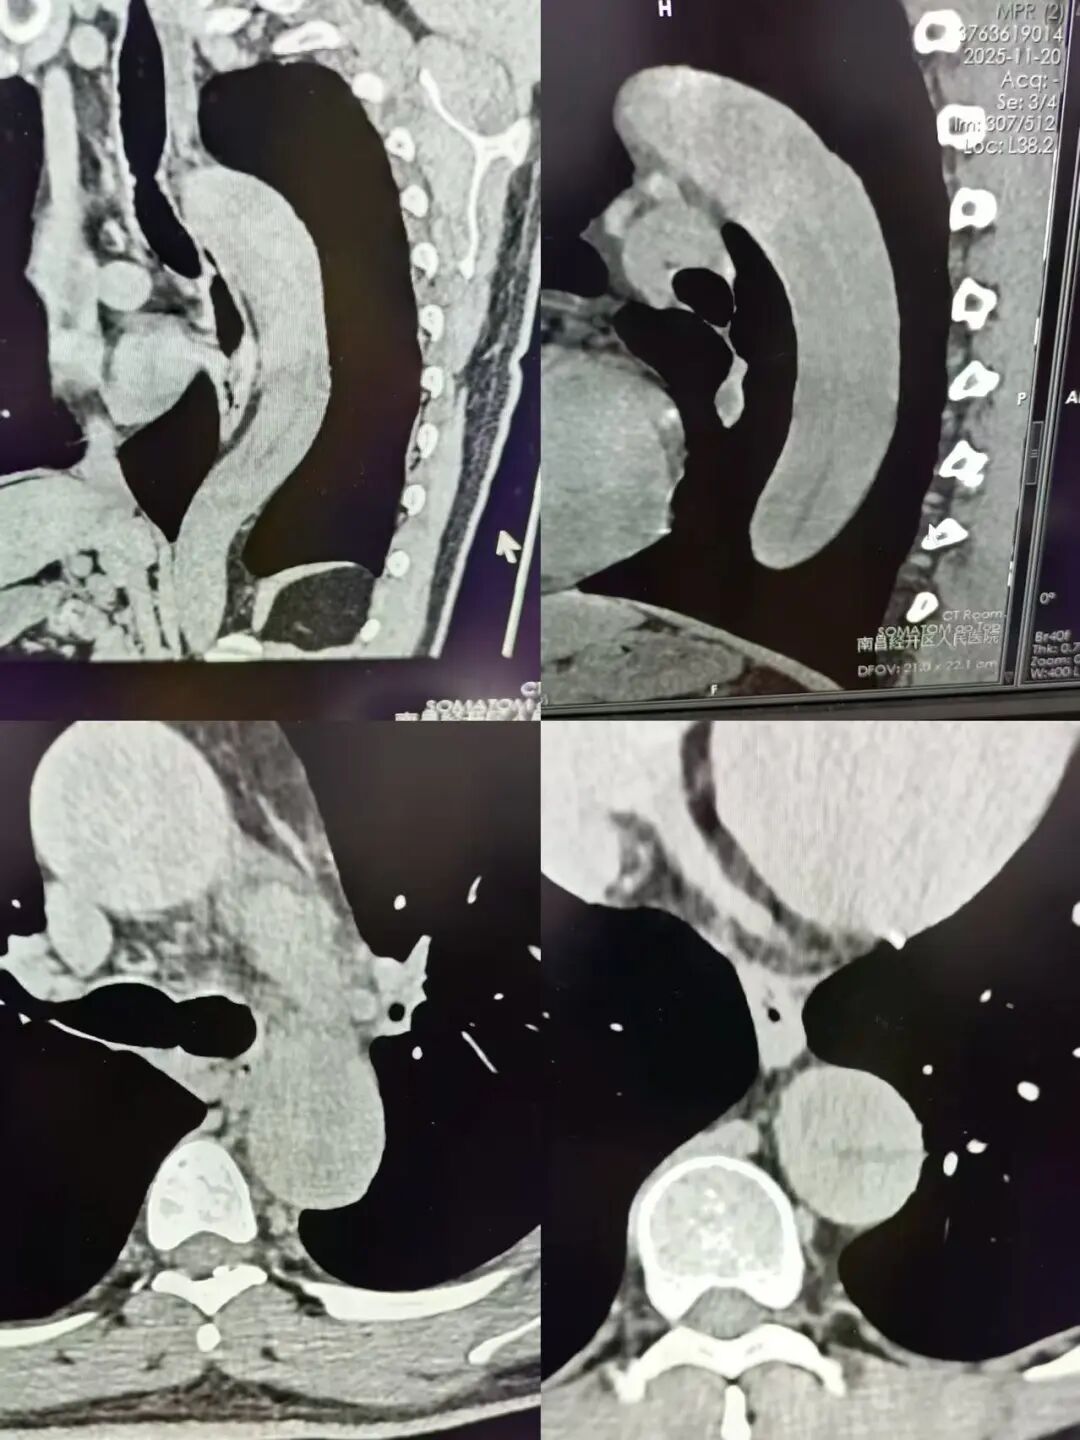

致命“血管炸弹”:主动脉夹层有多凶险? 主动脉夹层被医学界称为“移动的血管炸弹”,是死亡率极高的急性心血管急症。正常主动脉由内膜、中膜、外膜三层结构组成,当内膜因高压血流撕裂,血液会冲入中层与外层之间形成“假腔”,一旦外层破裂,24小时内死亡率超50%,且每延迟1小时救治,风险就增加1%,堪称“生死竞速”的急症。 更棘手的是,这类急症的早期诊断难度极大。普通CT平扫因缺乏足够对比度,难以清晰显示内膜撕裂口、假腔等关键病变,仅凭肉眼观察极易造成漏诊。临床确诊需依赖增强CT检查,同时高度考验影像科医生的临床经验积淀与图像质量把控能力,任何一丝细微的疏忽,都可能错失最佳救治时机。 十分钟精准研判,多科联动紧急转运 11月20日,江先生因突发剧烈胸痛、难以忍受,紧急前往我院就诊。影像科医生涂国平接诊后,凭借对急性重症的高度警惕性和多年积累的丰富临床经验,当即判断情况危急。诊断过程中,涂医生发现该病例非常不典型,无常见的钙化内移征像,凭丰富的影像阅片经验,认真仔细观察,发现有线状血管间隔后多平面重建,确定为主动脉夹层!从检查完成到出具明确诊断报告,全程仅用十分钟,并第一时间启动医院紧急预警机制。 “时间就是生命,必须立即联动!”涂国平医生当即拨通急诊科电话,详细说明病情凶险程度。急诊科快速响应,协调救护车、联系转诊医院,各环节无缝衔接,救护车火速到位,医护人员一路护送,将江先生安全转往上级医院接受针对性治疗,为后续抢救赢得了黄金时间。 从精准诊断到紧急转运,我院用高效协作与责任担当,成功遏制了“血管炸弹”的致命威胁,充分彰显了我院急救体系的硬核实力。 健康提示:胸痛不止是“小毛病”,及时就诊是关键! 主动脉夹层发病急、进展快,早期症状多表现为突发剧烈胸痛,易被误认为普通胃痛、心绞痛,从而延误就医。在此提醒广大市民:一旦出现胸痛、胸闷、背痛等不适症状,切勿拖延,需立即前往正规医院就诊,避免因忽视病情导致严重后果。